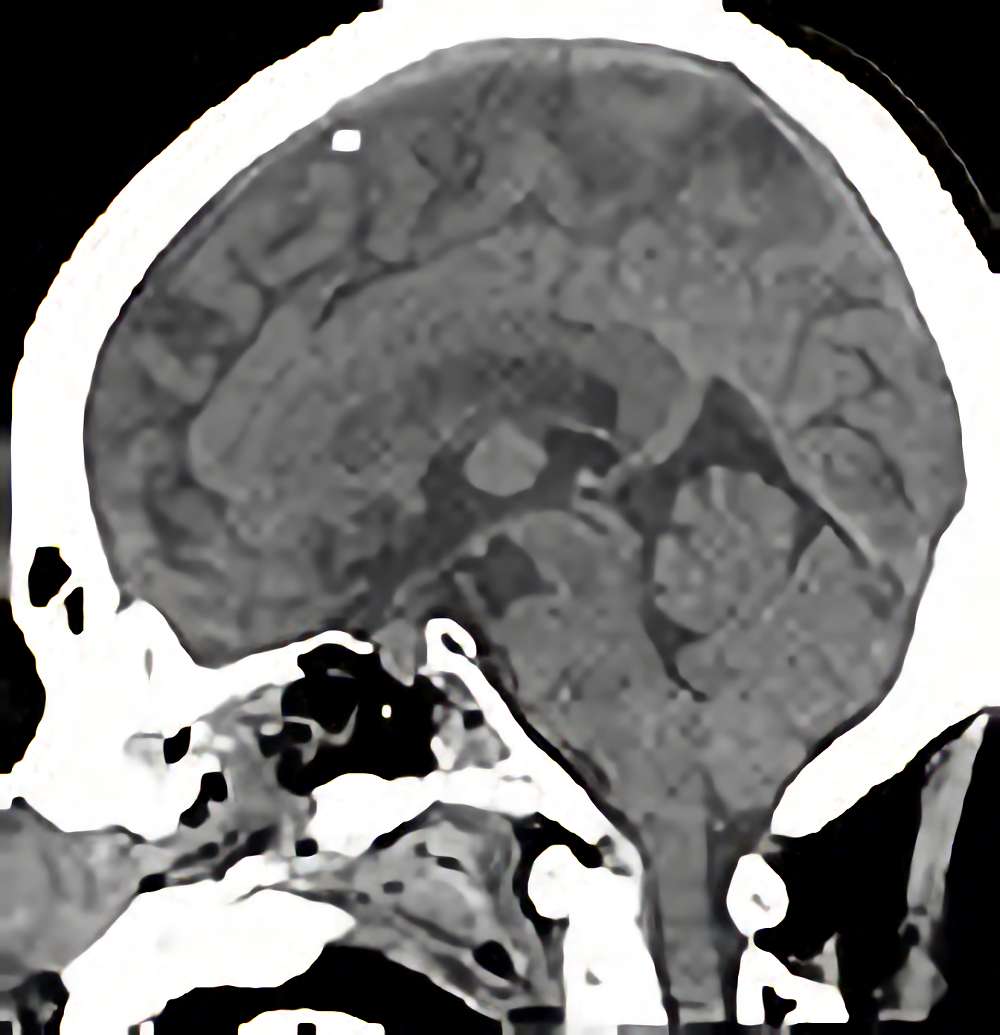

下垂体腺腫

断層撮影

手術前1

No.’12_29 手術前1

No.’12_29 手術後